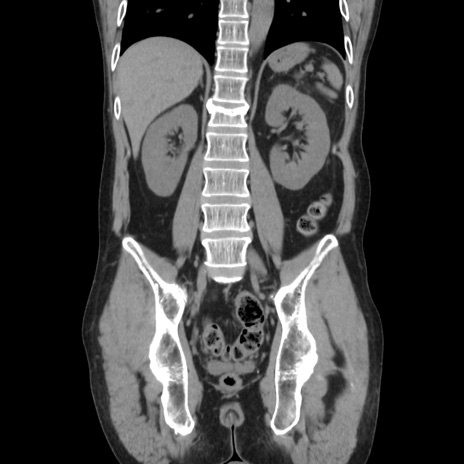

症例37(冠状断像)

【症例】40歳代 男性

【主訴】腹痛

【現病歴】4時間ほど前に電車に乗車中に臍部上より腹痛出現。徐々に増悪し起立困難となり、救急外来受診。生ものは数日食べていない。今朝お雑煮を食べた。

【身体所見】BT 36.8℃、BP 117/84mmHg、HR 91/min、SpO2 97%、苦悶様、腹部:臍上部広範囲圧痛あり、反跳痛±

【データ】WBC 8100、CRP 0.03